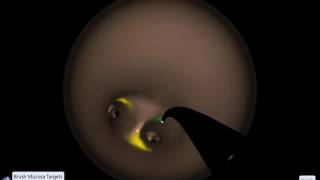

EndoSim Bronchoscopy: Cytology

EndoSim Bronchoscopy: Cytology EndoSim Bronchoscopy: Biopsy

EndoSim Bronchoscopy: Cytology

EndoSim Bronchoscopy: Cytology EndoSim Bronchoscopy: Biopsy